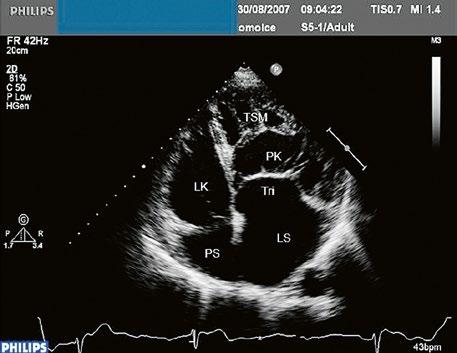

Poslechový nález systolického šelestu nad plicnicí s fixním rozštěpem 2. ozvy je nenápadný. Echokardiograficky je patrná dilatovaná a objemově přetížená pravá komora s paradoxním pohybem septa (Obr. 45.9), zkratový tok může být vidět i transtorakálně (TTE) (Obr. 45.10, Video 45.3, Video 45.7), ale suverénní diagnostickou metodou je jícnová echokardiografie (TEE), případně s 3DE zobrazením (Obr. 45.1, Obr. 45.2,

Obr. 45.10 TTE, čtyřdutinová apikální projekce s levo pravým zkratem na úrovni síní (šipka) při defektu septa síní typu secundum PK – pravá komora, LK – levá komora, LS – levá síň, PS – pravá síň

Obr. 45.9 M mode, paradoxní pohyb septa při objemovém přetížení pravé komory u defektu septa síní typu II s levopravým zkratem